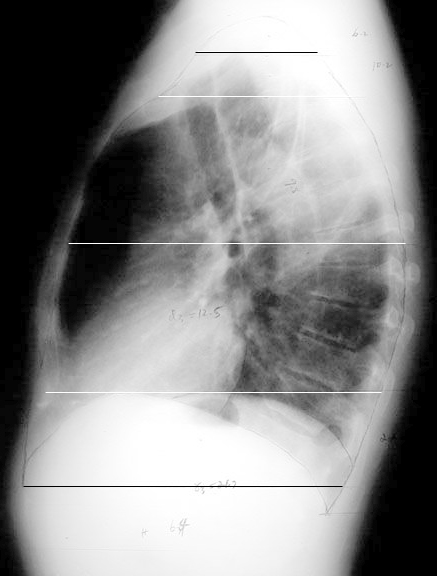

Radiologic Total Lung Capacity